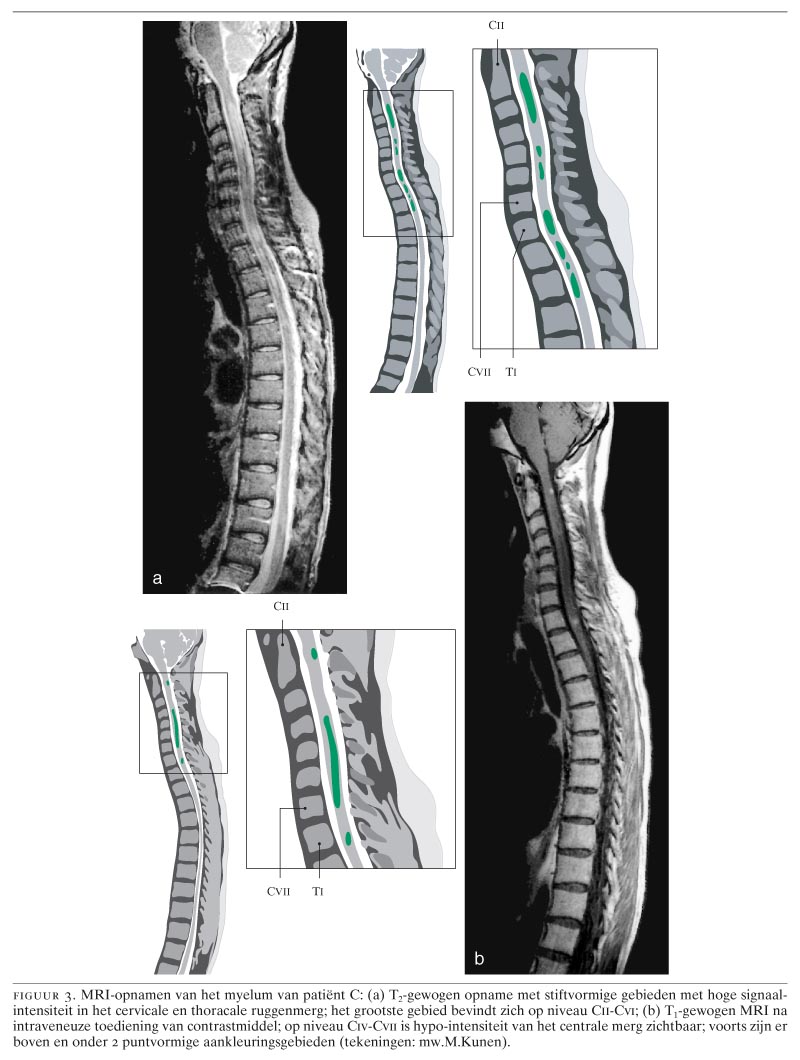

Neuromyelitis Optica Ziekte Van Devic Een Zware Variant Van Multiple Sclerose Nederlands Tijdschrift Voor Geneeskunde